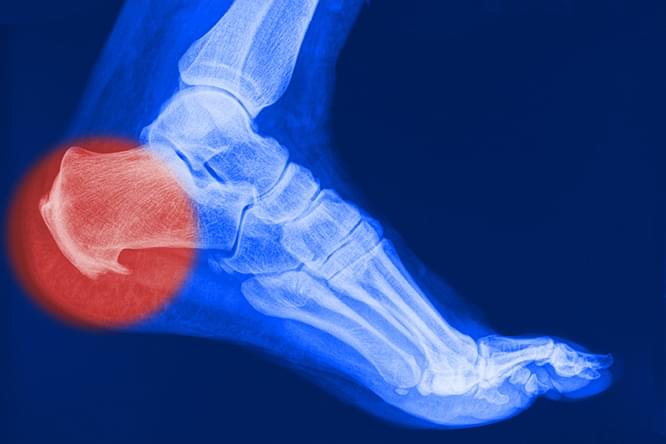

Все это явялется симптомами плантарного фасциита или более знакомого нам синдрома «пяточной шпоры». В большинстве случаев болевой синдром обусловлен воспалительно-дегенеративными изменениями плантарной (подошвенной) фасции.

Активность человека снижается, воспалительный процесс затухает и на месте поврежденных волокон возникают костные разрастания, которые видны на рентгенограмме и имеют характерный вид «шпоры»

Вот поэтому это заболевание и называют «пяточной шпорой», хотя сама «шпора» является уже результатом длительно протекающего плантарного фасциита.

Рентгенография

Рентгенография пяточной области необходима для исключения перелома, если в анамнезе есть указания на травму. На ранних этапах формирования пяточная шпора на рентгенограмме не визуализируется.